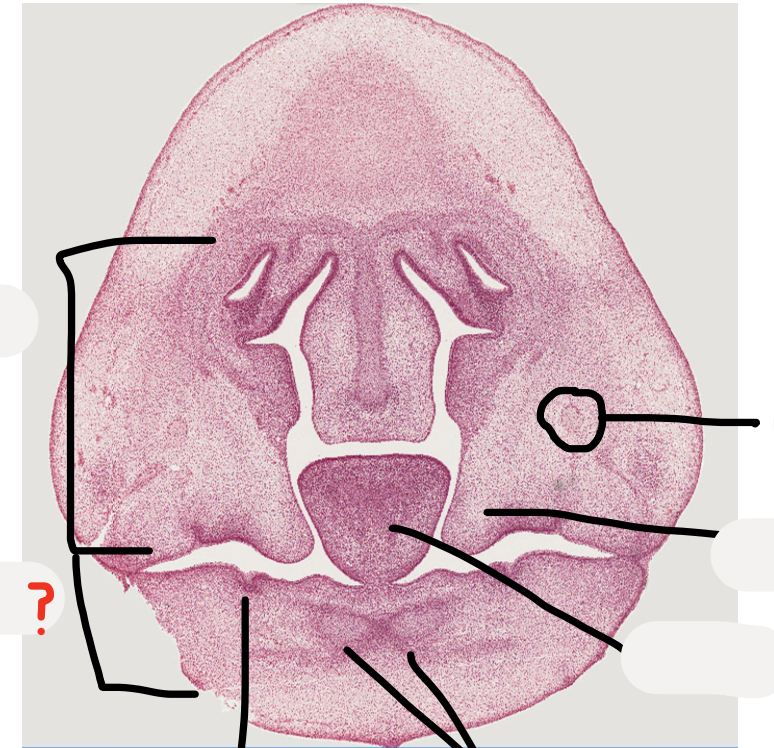

39

what are these?

Remnants of nasal capsule

40

Condensed ectomesenchymal cells that will make dentine and pulp

41

Epithelial cells that will form ameloblasts and make enamel